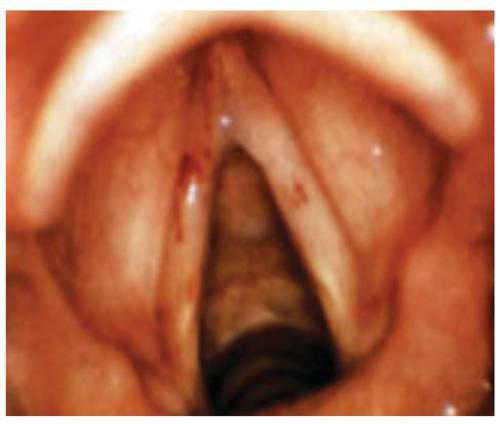

При ларингос копии гиперемия, отечность слизистой оболочки гортани и голосовых связок. Под складочный ларингит ложный круп.

В гортани при ларингос копии можно обнаружить кровоточащие участки. Существует также туберкуле зный ларингит, он возникает при распространении туберкулеза легких. При таком ларингите образуются утолщения в виде бугорков.

Пациенты ощущают сухость во рту, им кажется, что в гортани находится какое то инородное тело. Голос быстро устает, после не длительного общения появляется охриплость. При ларингос копии отмечается застойная гиперемия слизистой. Можно обнаружить слизь в просвете гортани. Характеризуется хронической гиперплазией слизистой оболочки гортани. Бывает ограниченный и диффузный. Основной жалобой ларингита является охриплость голоса, может возникнуть даже его отсутствие. В период обострения заболевания признаки такие же как у катарального ларингита. Можно наблюдать симметричные выступы на голосовых связках. При ларингос копии наблюдается гипертрофия слизистой, можно обнаружить симметричные выступы. Он связан с недоразвитием слизистой оболочки носоглотки, иногда может возникать после перенесенной скарлатины или дифтерии.